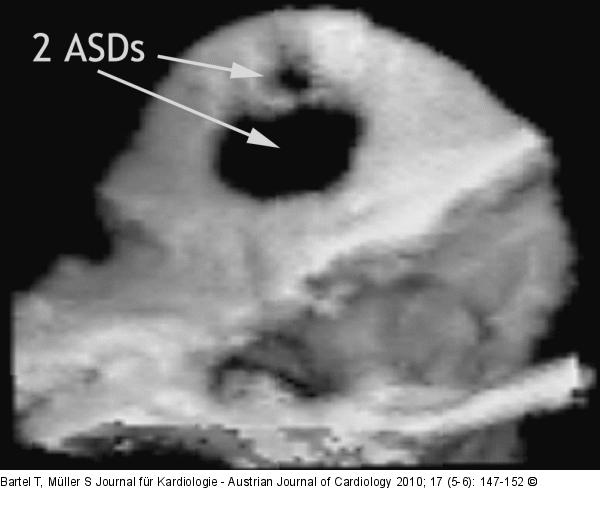

Abbildung 7: Vorhofseptumdefekt Zwei Vorhofseptumdefekte (eine größere und eine benachbarte kleinere interatriale Kommunikation) in der dreidimensionalen Aufblickdarstellung aus dem linken Vorhof. |

Zwei Vorhofseptumdefekte (eine größere und eine benachbarte kleinere interatriale Kommunikation) in der dreidimensionalen Aufblickdarstellung aus dem linken Vorhof. |